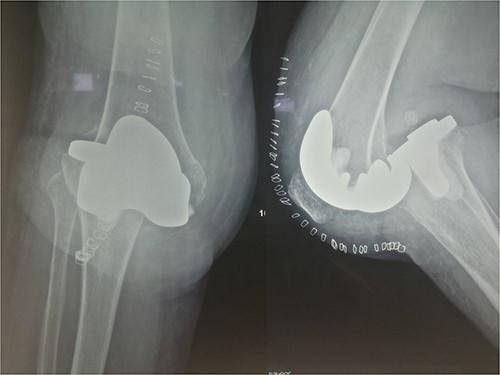

An 86-year-old female patient with a body mass index (BMI) of 31.2 presented to our outpatient department with severe right knee pain. Physical examination revealed a mechanical block of the knee, limiting its range of motion (ROM) between 10° and 55° of flexion. Plain knee radiographs showed grade 4 knee osteoarthritis (OA) in the Kellgren–Lawrence scale (Fig. 1).

The patient underwent a medial-pivot design TKA (Evolution Medial-Pivot Knee System, Microport, China). Intraoperatively, a full ROM was achieved only after extensive soft tissue and bone releases. The extension gap was limited by significant hamstring spasticity, and a proper extension gap was attained after additional anterior femoral cut. Early postoperative recovery was uneventful (Fig. 2). On the third postoperative day, the patient complained of severe knee pain accompanied by excessive swelling during kinesiotherapy. Clinical examination showed a posterior sag sign at 30° of flexion (Fig. 3). No signs of neurovascular deficit were obvious. A knee X-ray revealed posterior TKA dislocation and a small, non-displaced femoral fracture (Fig. 4). The tibial component was reducible, but redislocation occurred with the knee extended over 90°, indicative of severe instability. Laboratory investigations, including erythrocyte sedimentation rate and C-reactive protein, were normal. A knee arthrocentesis was performed with no substantial findings. Two botulinum toxin injections (200 IU) to the hamstrings were performed without improvement. Local muscle hypertonia was evaluated through a neurological examination and a brain computed tomography scan, with no remarkable findings. The patient’s history included intramedullary nailing of the right femur due to an intertrochanteric fracture 8 months before the TKA.